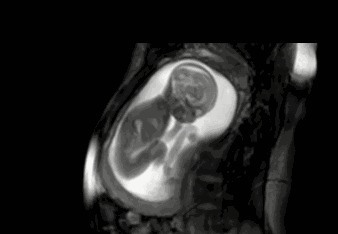

这么多项孕检,最让准妈妈们期盼的应该就是四维彩超大排畸了吧?虽然宝妈们纠结,担心宝宝万一要是有先天缺陷怎么办,但是这个检查能满足准妈妈和准爸爸的好奇心。宝宝到底长得像爸爸还是长得像妈妈,在妈妈的肚子里在做什么等等,在这个检查里都能看到。那么对于还没有到做思维的合适孕周的准妈妈们,你们是不是也好奇?我们有手机,我们可以玩手机,可以看书,可以听音乐,那宝宝呢?他会不会无聊呀?今天福林妈就来跟大家介绍一下。宝宝在妈妈的肚子里到底在做什么?做得最多的:睡觉

胎宝大多数时间都在睡觉。分为两种睡眠模式,安静型睡眠,约占整个孕期的20?活动型睡眠,约占整个孕期的60-70?安静型睡眠就是睡着之后不怎么动,活动型睡眠是睡着后,仍然在动。加在一起,孕期中,宝宝有80?0?时间在睡觉。剩下的10?0?时间,才是苏醒的时间。偶尔还会做梦有研究发现,宝宝在孕8个月大的时候,就会做梦了。

也许有人会问了,宝宝做没做梦,你又不是他,你怎么知道。这是一种推理得出来的结论。我们人类睡觉会有一个快速眼动期,通常做梦就发生在这个阶段。而胎宝8个月之后,睡觉的时候闭着眼,眼珠偶尔也会转来转去,所以才会推断宝宝也会做梦。但至于他做梦梦的什么,谁也不知道,你可以幻想一下,会不会是前世?吃饱喝好即使胎宝睡着,他也一样能吃。秘密武器就是那根链接着妈妈的脐带。脐带连接着胎盘,胎盘附着在子宫壁上,通过胎盘和脐带,妈妈体内的营养源源不断地供给给胎宝,维持着胎宝的营养。我一直觉得胎盘就像个吸盘,吸在妈妈的身体上,然后不断的从妈妈身体里吸养分,再用脐带传输给宝宝。宝宝不需要醒过来就能吃饱。

渴了就吞羊水。也不存在渴不渴的,毕竟他就泡在羊水里。宝宝吞羊水,其实是为了过滤羊水中的杂质,比如脱落的毛发、皮屑等等,吞下去羊水,通过自己的消化系统过滤一遍,然后再把过滤过的液体通过排尿的形式排放回去。所以,宝宝喝的羊水里,有自己的尿!可劲儿扑腾可劲儿玩水要说胎宝各个都是闭气冠军!在水里一泡就是280天,不用喘气的。因为他们不需要用肺呼吸,他们的氧气同样靠妈妈供给。在羊水里的他们就可以可劲儿地玩水扑腾。

之前也有爸妈做二维彩超的时候,看到胎宝在肚子里滑来滑去的。当时宝宝还比较小,活动空间很大,因为里面是有光滑的,还有水,所以胎宝就在里面划来划去,还会轻轻地蹬一下子宫壁借个力。静静地听妈妈的心跳声,是宝宝的“安眠曲”,听着心跳的声音,宝宝会特别安心。在胎宝24周的时候,听力基本形成,这时候就可以听到很多声音了。其中妈妈的心跳声是宝宝最常听到的声音。准妈妈和准爸爸在孕24周之后跟宝宝说话、唱歌、放音乐,胎宝都会听到哦,尤其是胎宝醒着的时候,跟胎宝说话,胎宝也会有反应呢。